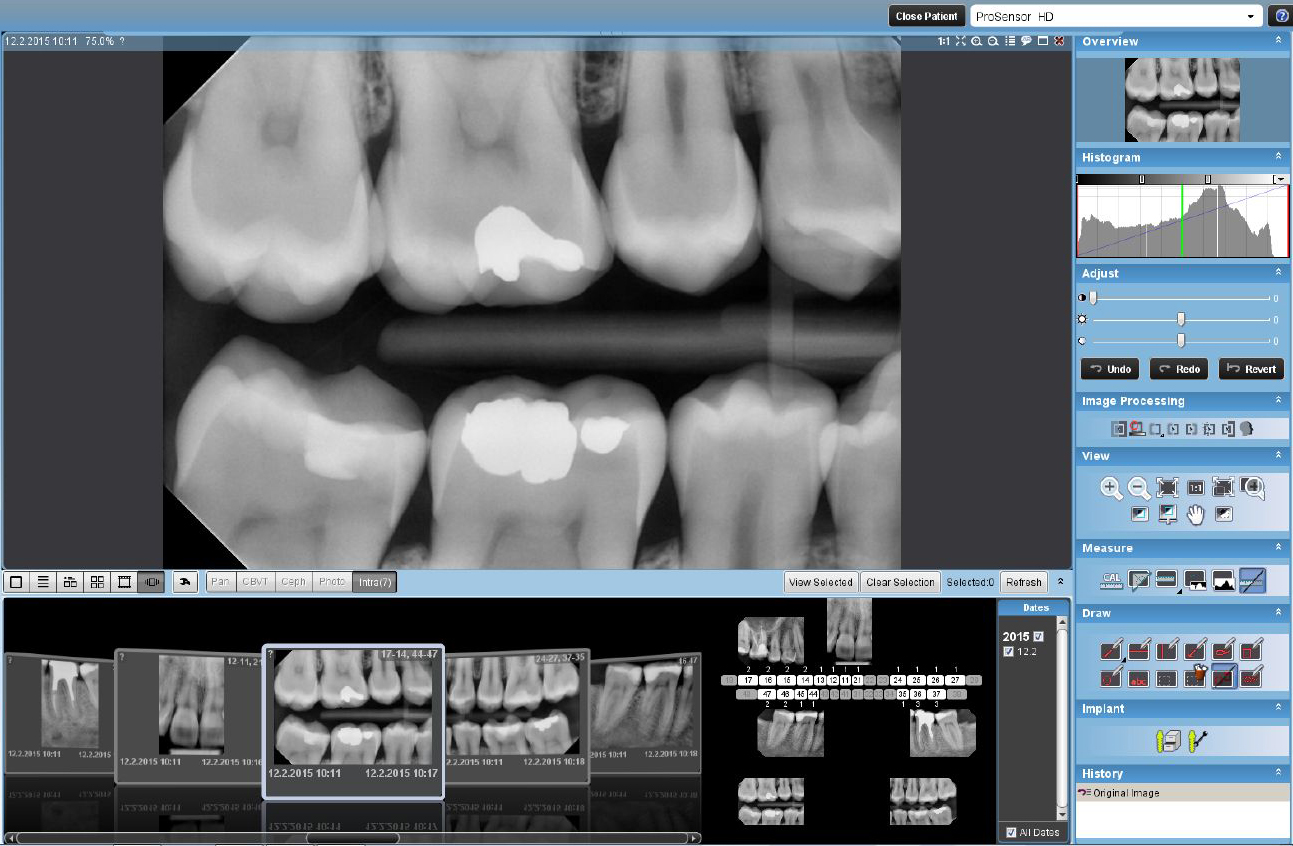

2D snimanje

Pored standardnog panoramskog programa, mogući su i poboljšani: interproksimalni program – prošireni kontakti između zuba za lakšu detekciju karijesa, poboljšani ortognalni program – sa jasno vidljivim alveolarnim grebenom za poboljšanu dijagnostiku parodontalnih oboljenja SmartPan – OPT snimak registrovan 3D senzorom. Sa istom efektivnom dozom dobija se 10 OPT snimaka pa se bira najpogodniji za dijagnostiku.

2D - SNIMCI